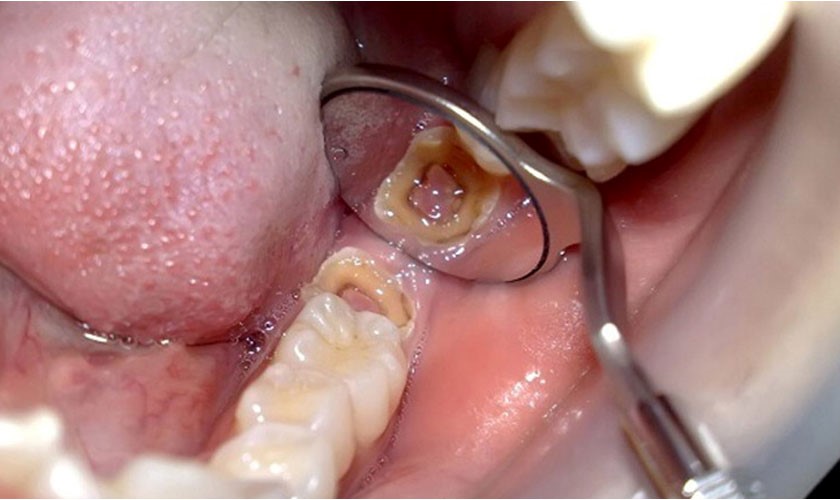

Nếu răng đã bị viêm tủy bác sĩ sẽ tiến hành loại bỏ tủy viêm. Sau đó kết hợp với thủ thuật trám để tạo hình lại mô răng giúp khôi phục lại tính thẩm mỹ và khả năng ăn nhai.

Bọc răng sứ sẽ được áp dụng cho trường hợp răng sâu vỡ lớn, tủy đã có viêm hoặc không. Bác sĩ sẽ tiến hành chữa tủy (nếu có) sau đó sẽ mài răng để tiến hành lấy dấu và chế tác mão sứ có kích thước phù hợp. Tiếp đến sẽ gắn mão sứ lên răng và tiến hành tinh chỉnh đến khi hoàn thiện. Răng sau bọc sứ sẽ giúp đảm bảo khả năng ăn nhai và tăng tính thẩm mỹ đáng kể.

(Ca lâm sàng chữa tủy kết hợp bọc sứ được thực hiện tại Peace Dentistry)(**)